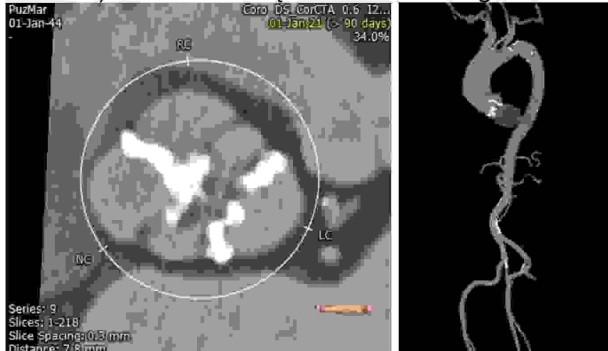

U 80-letniego chorego zdiagnozowano ciężką stenozę zastawki aortalnej na podstawie rutynowo wykonywanego badania echokardiograficznego. Ponadto badanie wykazało prawidłową funkcję obu komór przy nieistotnych wadach zastawek żylnych: mitralnej i trójdzielnej. Chorego skierowano na koronarografię przed planowaną interwencją w zakresie zastawki aortalnej, wykonując wcześniej badanie tomografii komputerowej (poniżej). Dotychczas chory funkcjonował samodzielnie, aktywnie spędzając wolne chwile (działka, rola), lecząc (z dobrym efektem) nadciśnienie tętnicze. Jest biologicznie młodszy. W zakresie leczenia wad zastawkowych serca: